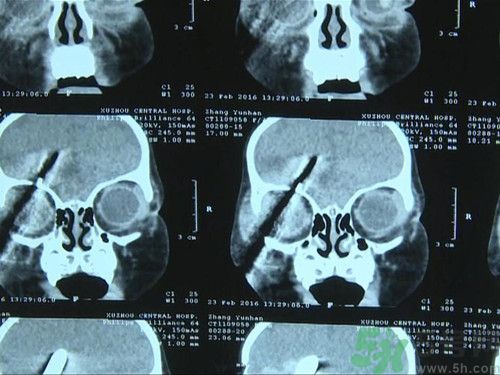

徐州女童名叫涵涵,今年只有1歲5個(gè)月。醫(yī)生發(fā)現(xiàn),螺絲刀已經(jīng)由面部斜插入涵涵的腦部,距離大血管僅有幾毫米。徐州市中心醫(yī)院腦外二科主任姜德華:“我看到這個(gè)小孩右側(cè)面部有一個(gè)螺絲刀從面部進(jìn)入插到頭部去了,從CT片子看,這個(gè)螺絲刀從眼眶部進(jìn)入到顱內(nèi),大概進(jìn)入頭面部有7厘米,其中進(jìn)入到顱內(nèi)有3厘米。小孩是昏迷的?!?/p>